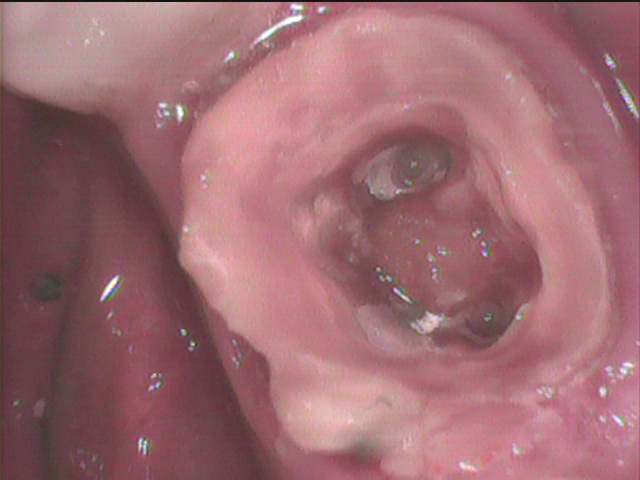

2本取れた

なんと根管充填・・根管治療の最後の過程 がありません。

除去後に驚き 先端までレジンが入っています。

根管充填がなければ、根管治療をしたことになりません。

根管内に根管治療をした形跡がありませんでした。